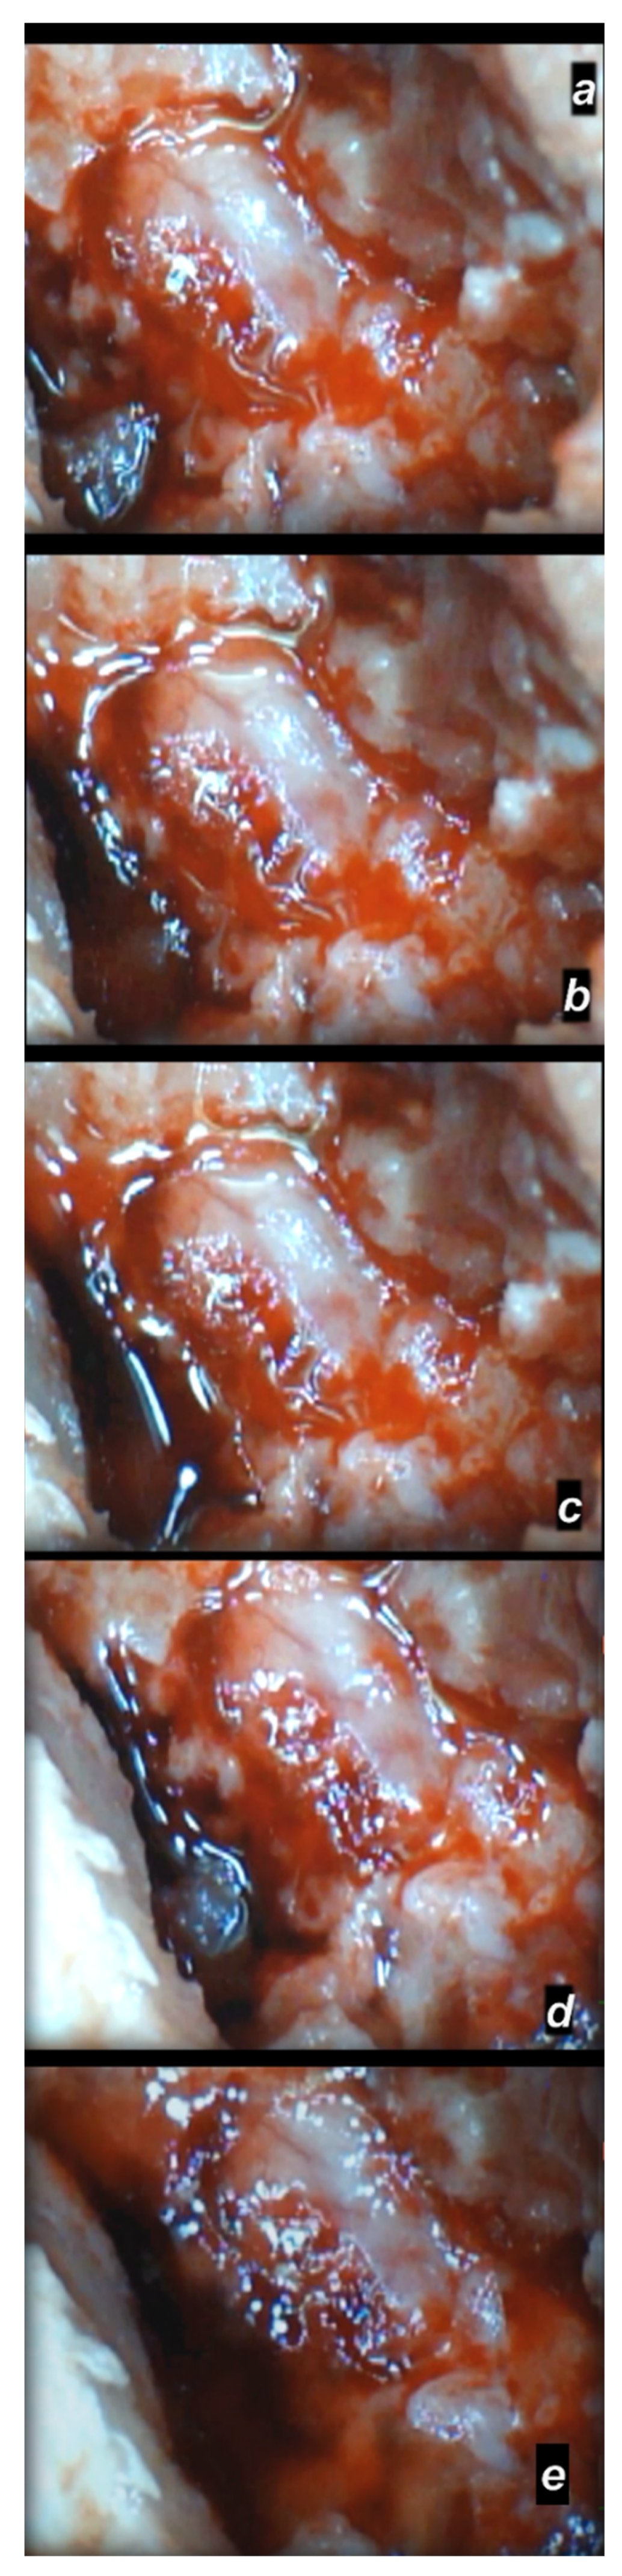

3.2. Microscopy

3.2.3. Delayed Post-Injury Course, Long-Term Effect